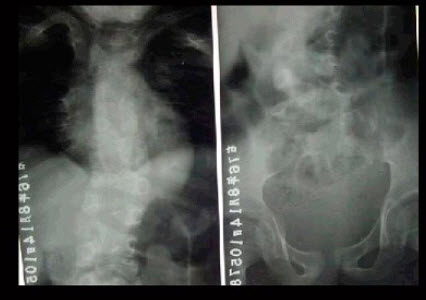

29、单项选择题

男,15岁,右髋部疼痛、红肿,有压痛,皮温增高,结合图像,最可能的诊断是()

A.骨肉瘤

B.急性骨髓炎

C.尤文肉瘤

D.转移性神经母细胞瘤

E.骨结核